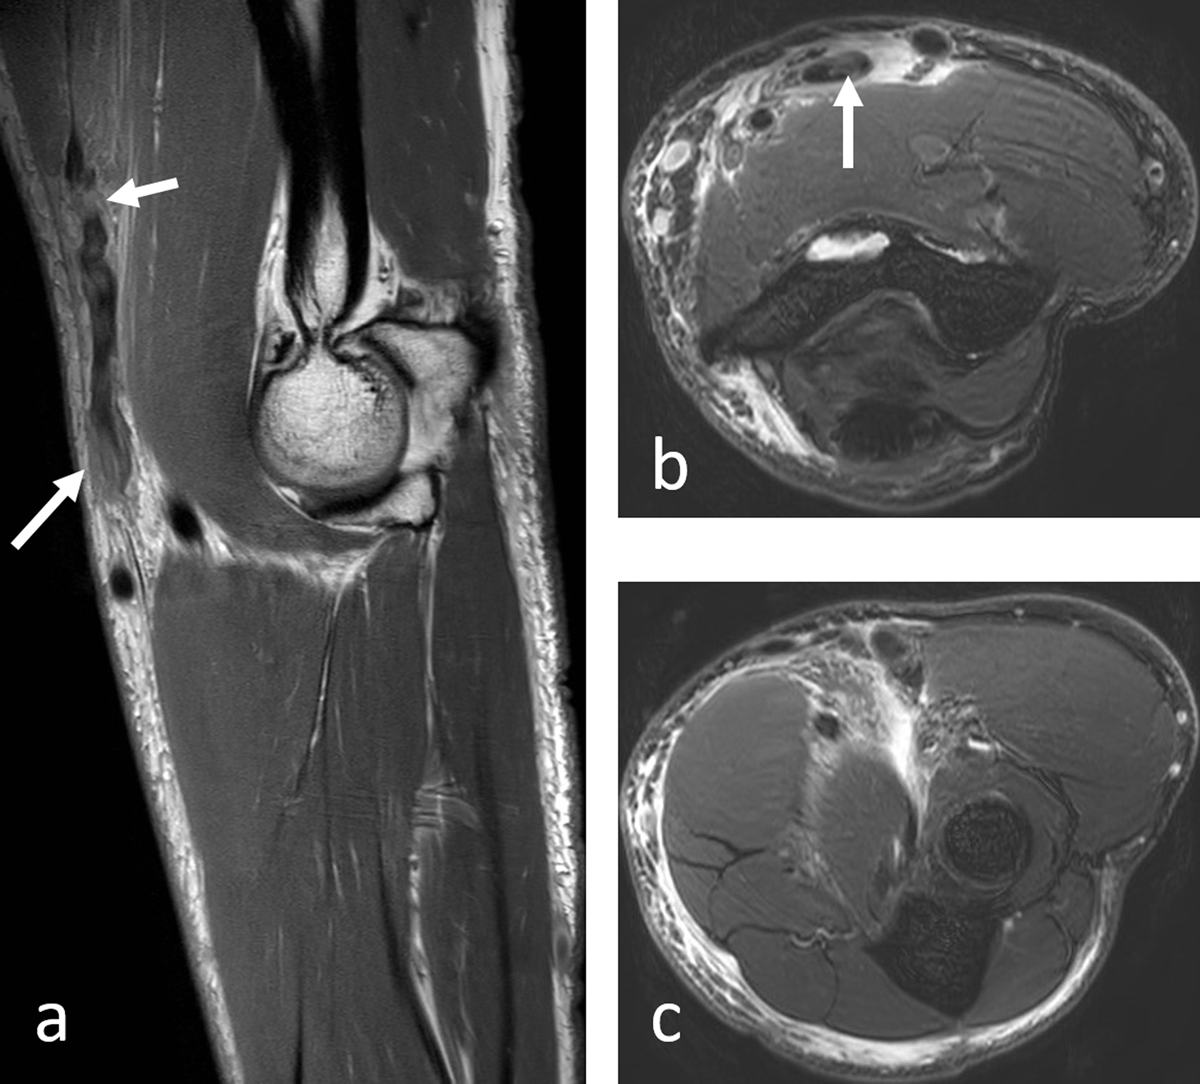

Figure 2a–c

Complete posttraumatic rupture of the DBBT and of the lacertus fibrosis with retraction of the proximal stump and intratendinous areas of increased signal on sagittal T1-weighted and axial proton-density fat-saturated images (arrows) and with surrounding high signal fluid collection on the axial views. The tendon was surgically refixed by two anchors.